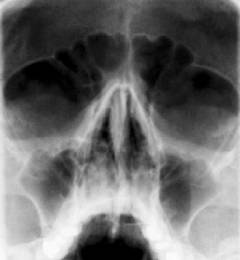

- хронический насморк, хронические синуситы (воспаление придаточных пазух носа, например, гайморовых — гайморит).

- Оценка носового дыхания. Врач выявляет сопутствующий трахеиту насморк.